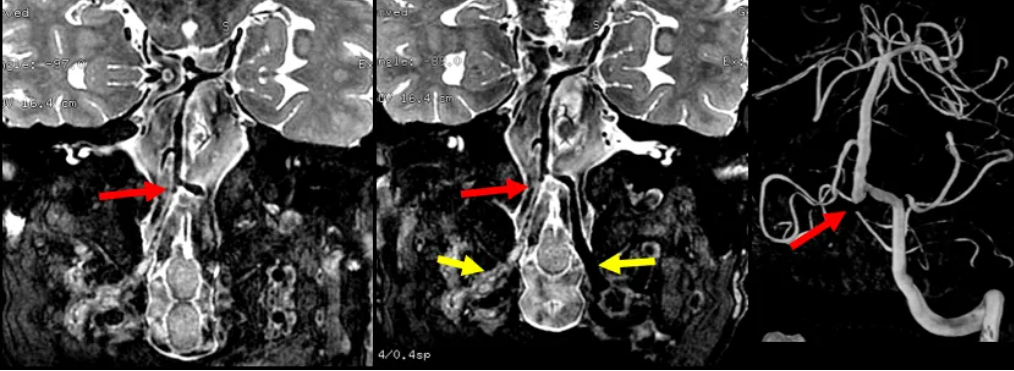

三、CTA检查

双侧颈内动脉虹吸段中度狭窄;

右侧椎动脉未见显影;

基底动脉汇合处一类圆形囊性凸起;

CTA示椎基底动脉汇合处一类圆形囊性凸起,根据凸起位置有理由怀疑是闭塞的椎动脉残余,但不能明确诊断,动脉瘤不除外。